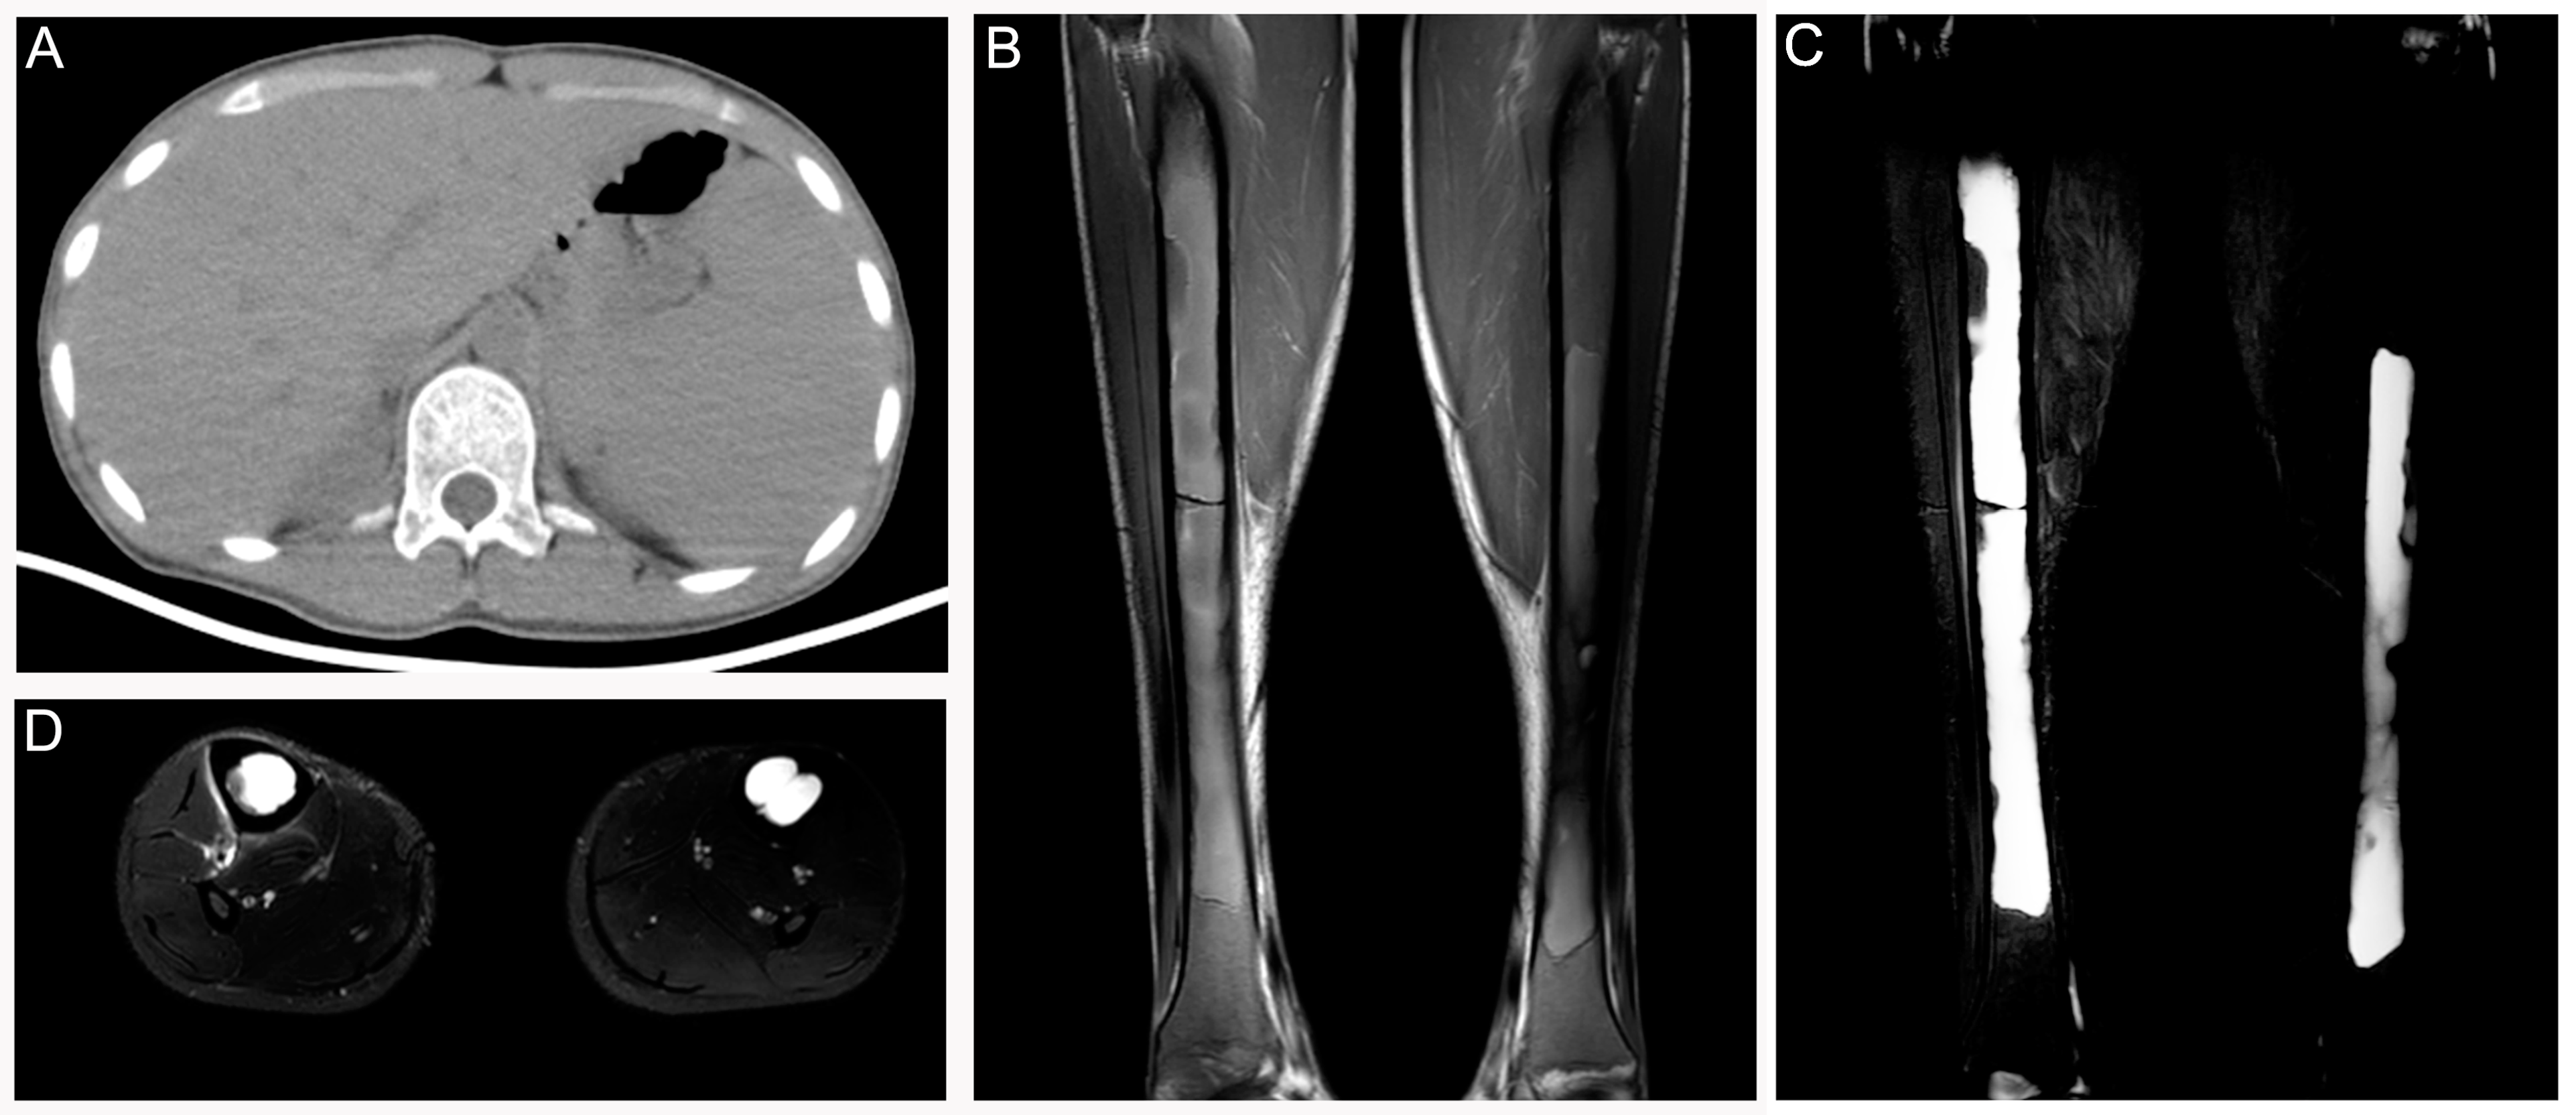

3.3. Steroid-Induced Osteonecrosis

3.4. Progressive Diaphyseal Dysplasia (PDD)

3.5. Erdheim–Chester Disease (ECD)

3.6. Langerhans Cell Sarcoma